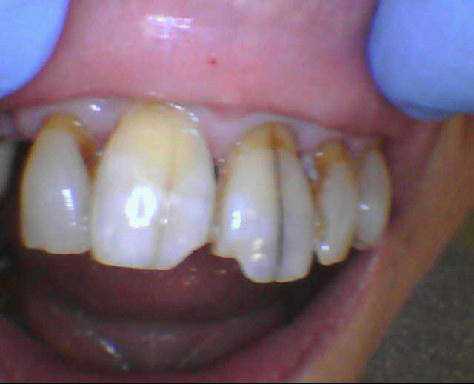

apres avoir lui avoir reglé la parafonction , , cette pré-mamie me demande de faire quelque chose pour ses fêlures pas jolies .

si je lui fais 2 facettes , comment gerer le prov ????

des idées sur la forme de préparation ?

Et popurquoi pas 4 facettes? la 12 n'est pas nickel non plus, ça sera plus facile pour gérer l'esthetique, non?

et si je tailles le retour du bord libre , la difference d epaisseur ne va pas me donner des différences de rendu de teintes ?

avec le diasteme il va falloir rentrer bien en proxy , bien tailler le bord libre et donc retour pour mes reglages ,